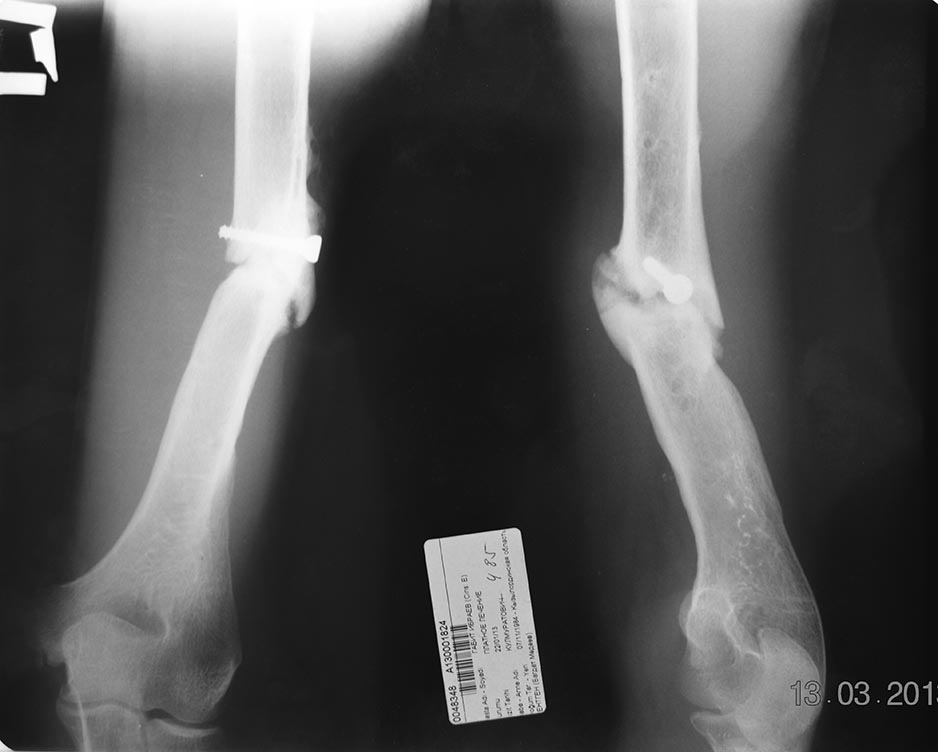

Уважаемые коллеги! Пациент  Г  29 лет.  2009 году оперирован в одной из

ЦРБ с диагнозом закрытый перелом средний трети плечевой кости.

Произведено открытая репозиция,экстрамедуллярный некорректный

металлоостеосинтез (фиксация 4 винтами). 2010 году  в ОКБ по поводу

ложного сустава и нестабильностью металлоконструкции произведено  ЧКДО

аппаратам Илизарова +костная аутопластика. В данный момент имеется

угловая деформация плеча и незн болезненность в проекции деформации.

Клинический признаки воспаления и потологический подвижность нет, но

рентгенологический признаки слабой консолидации и угловой деформации.

Планируем удаление винта, рассверливание КМК, БИОС плечевой кости +

аутопластика.